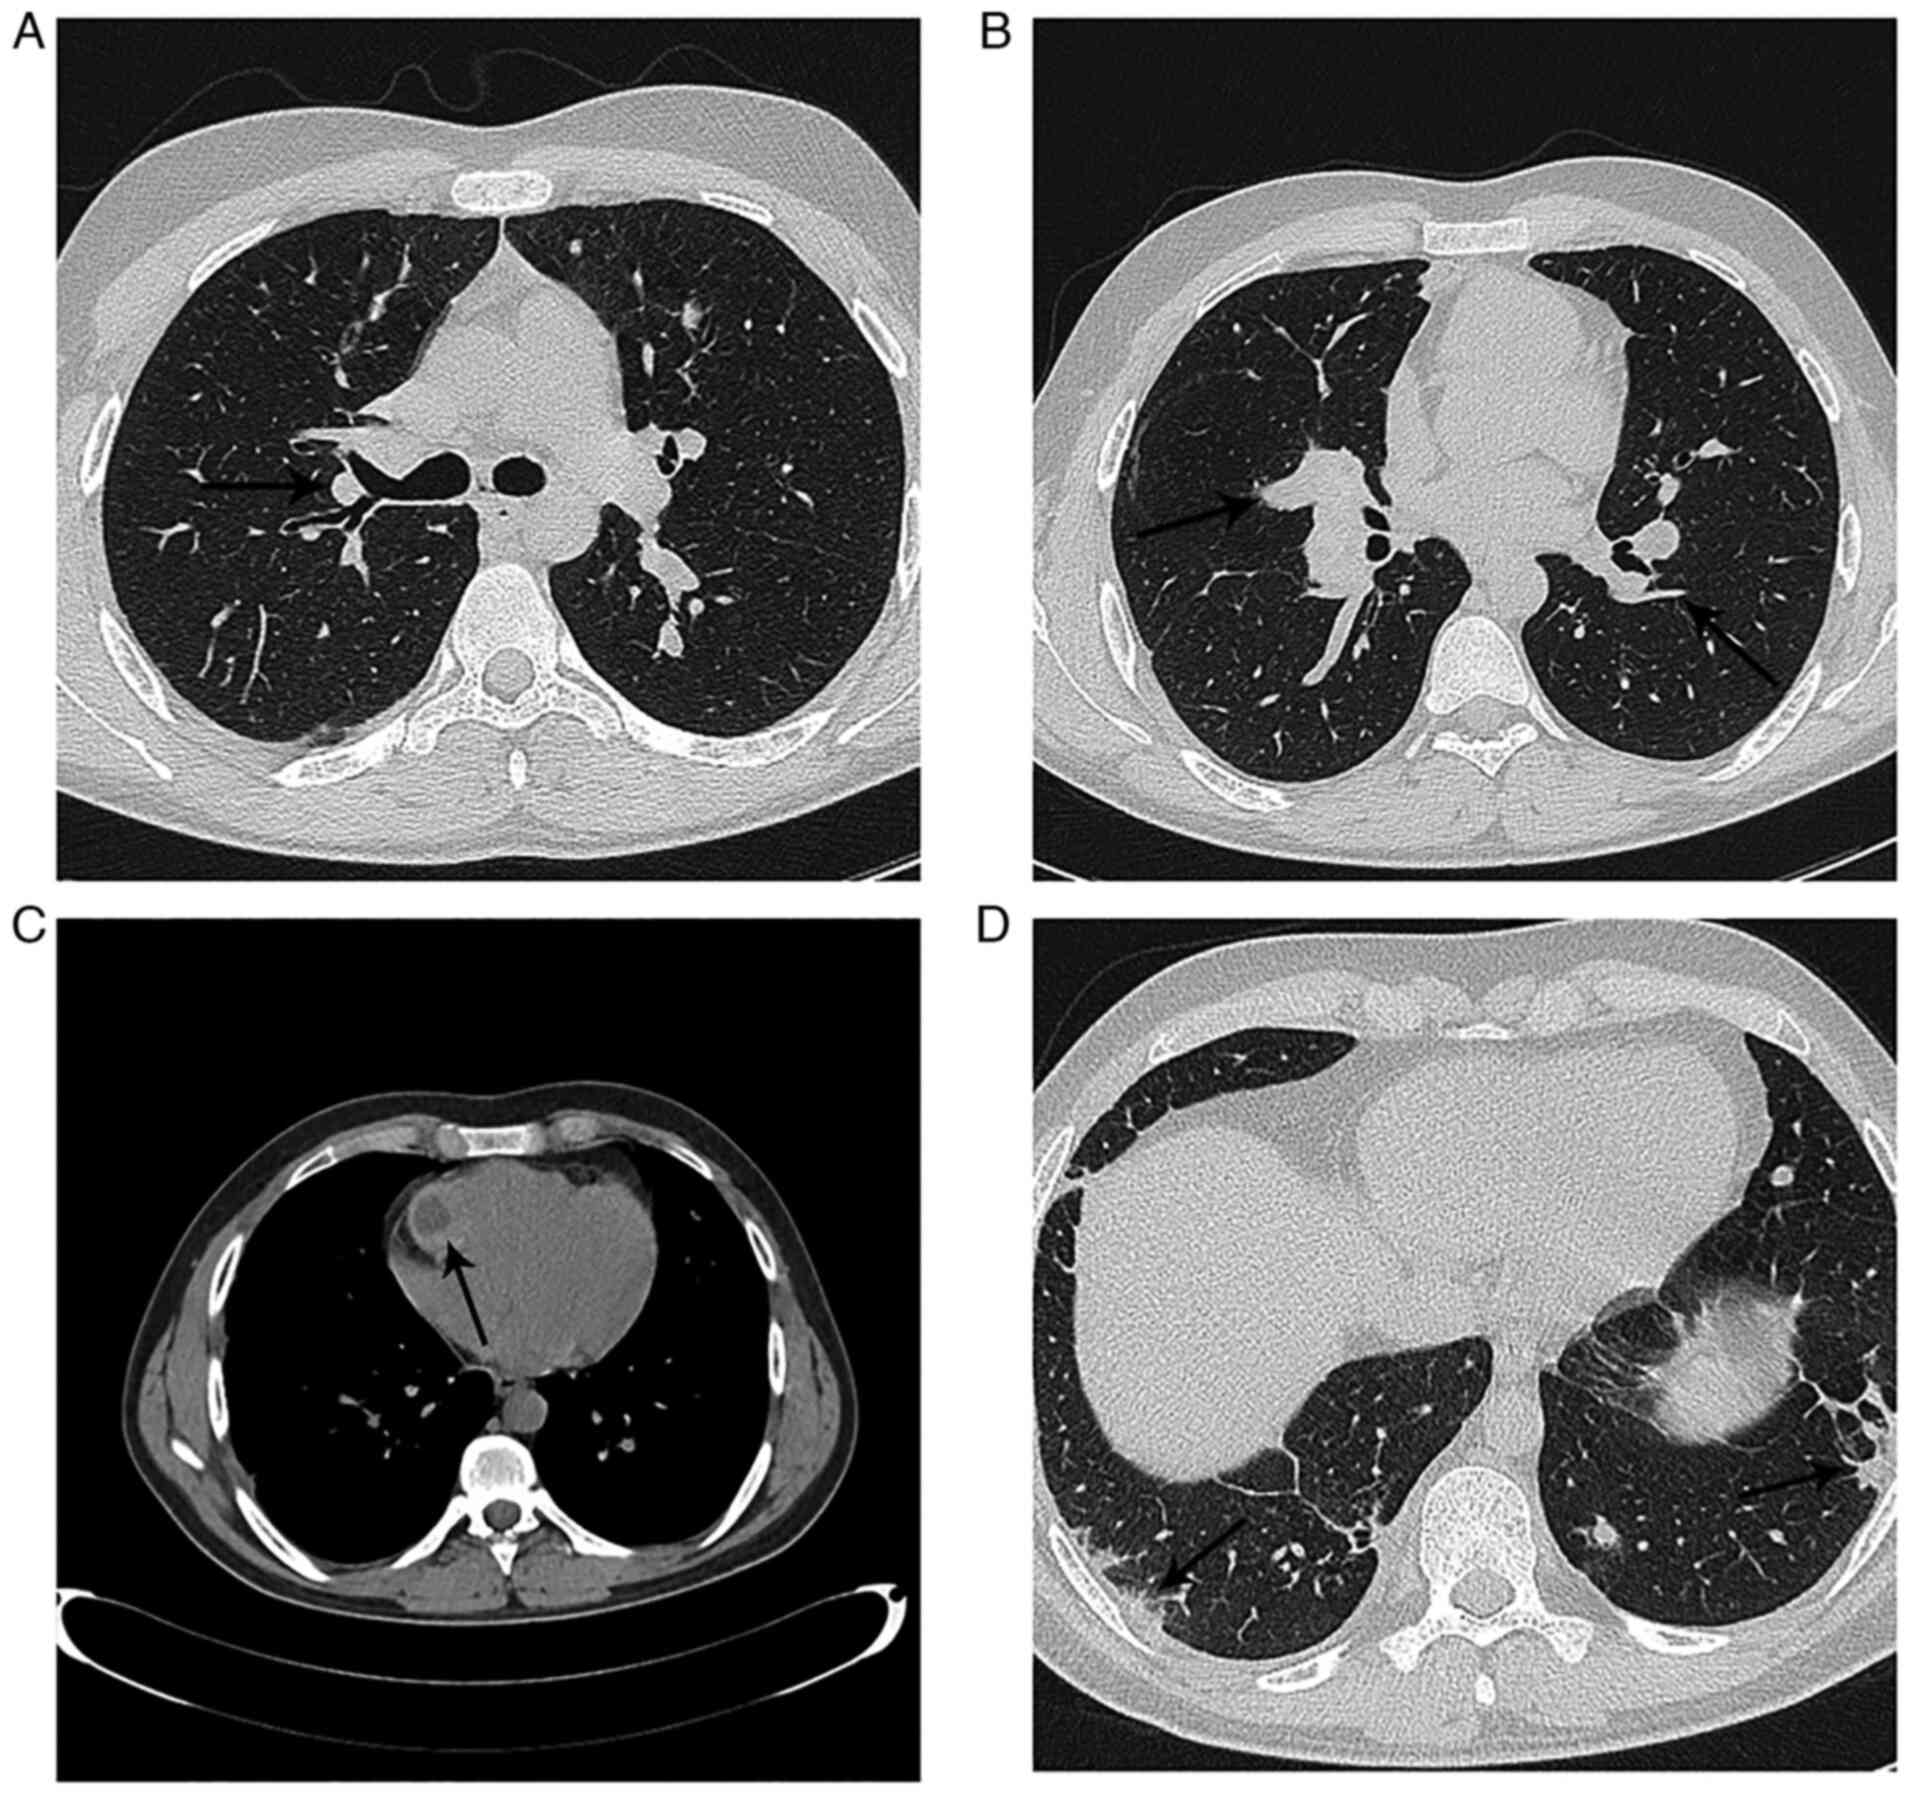

The case of a 19-year-old male from a rural area, who was admitted to a local Emergency Department (Hospital of Buzau, Buzau, Romania) in April 2016 with anaphylactic shock, is presented. Considering the patient's symptoms, including a mild fever (37.5˚C), sharp right-sided thoracic pain and a dry cough, he was referred to the Department of Pneumology. Chest radiography indicated left lower lobe pneumonia and as the patient's CURB-65 (scored based on confusion; BUN, >20 mg/dl; respiratory rate, ≥30 breaths/min; blood pressure: Systolic, <90 mmHg; diastolic, ≤60 mmHg; and age, ≥65 years) score was 0, the patient received amoxicillin and clavulanic acid (875/125 mg) twice-daily for 7 days and was discharged. Over the next 10 days the patient's symptoms worsened and he was admitted again to the same hospital and a pulmonary CT scan was performed. The pulmonary CT-scan demonstrated a bilateral pulmonary embolism of the segmental arteries (Fig. 1A and B), as well as a cystic mass on the right ventricular free wall (Fig. 1C). The patient was therefore referred to the Department of Cardiology of the ‘Coltea’ Clinical Hospital (Bucharest, Romania).

Figure 1

Pulmonary CT scan presenting (A) bilateral central pulmonary nodules, (B) a bilateral pulmonary embolism of the segmental arteries, (C) a mass on the right ventricle free wall and (D) subpleural pulmonary nodules.

After the first year, the patient was lost to follow-up for 2 years, and during the subsequent year, the patient presented at the Department of Pneumology with hemoptysis after abandoning the antiparasitic treatment. A pulmonary CT-scan showed bilateral central pulmonary nodules and subpleural pulmonary nodules (Fig. 1D) and the patient was referred for thoracic surgery where four hydatid cysts were excised. Histological analysis confirmed the presence of pulmonary hydatid cysts (Fig. 4) and it was recommended that the patient resume antiparasitic treatment.